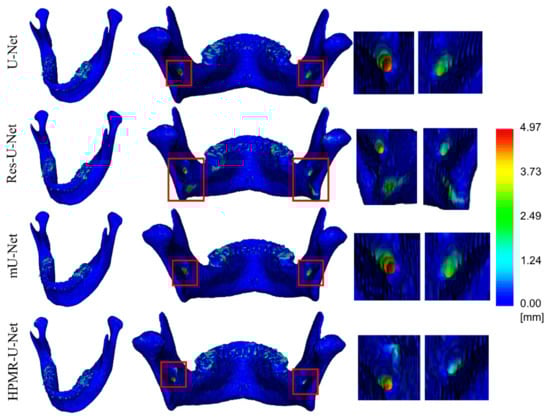

| U-Net | 98.3 ± 0.4 | 0.4 ± 0.1 | 0.0 ± 0.0 | 63.4 ± 20.2 | 7.3 ± 5.8 | 1.8 ± 3.5 | 62.8 ± 26.3 | 9.6 ± 11.8 | 3.2 ± 7.9 | 61.2 ± 17.9 | 33.7 ± 26.1 | 4.1 ± 4.0 |

| Res-U-Net | 98.2 ± 0.4 | 0.4 ± 0.1 | 0.1 ± 0.0 | 51.3 ± 20.1 | 13.5 ± 12.3 | 2.0 ± 1.8 | 46.3 ± 25.5 | 18.0 ± 19.8 | 6.5 ± 13.5 | 48.5 ± 13.1 | 28.8 ± 20.6 | 4.1 ± 3.3 |

| mU-Net | 98.4 ± 0.3 | 0.4 ± 0.0 | 0.0 ± 0.0 | 72.3 ± 21.6 | 5.6 ± 6.4 | 1.5 ± 3.5 | 71.4 ± 27.8 | 8.4 ± 12.9 | 2.5 ± 5.0 | 63.6 ± 14.7 | 22.5 ± 18.9 | 2.6 ± 2.2 |

| HPMR-U-Net | 97.4 ± 0.4 | 0.4 ± 0.1 | 0.1 ± 0.0 | 86.5 ± 3.9 | 1.8 ± 1.3 | 0.2 ± 0.1 | 86.4 ± 6.2 | 2.8 ± 7.7 | 0.3 ± 0.7 | 77.7 ± 4.1 | 3.4 ± 0.6 | 0.7 ± 0.2 |